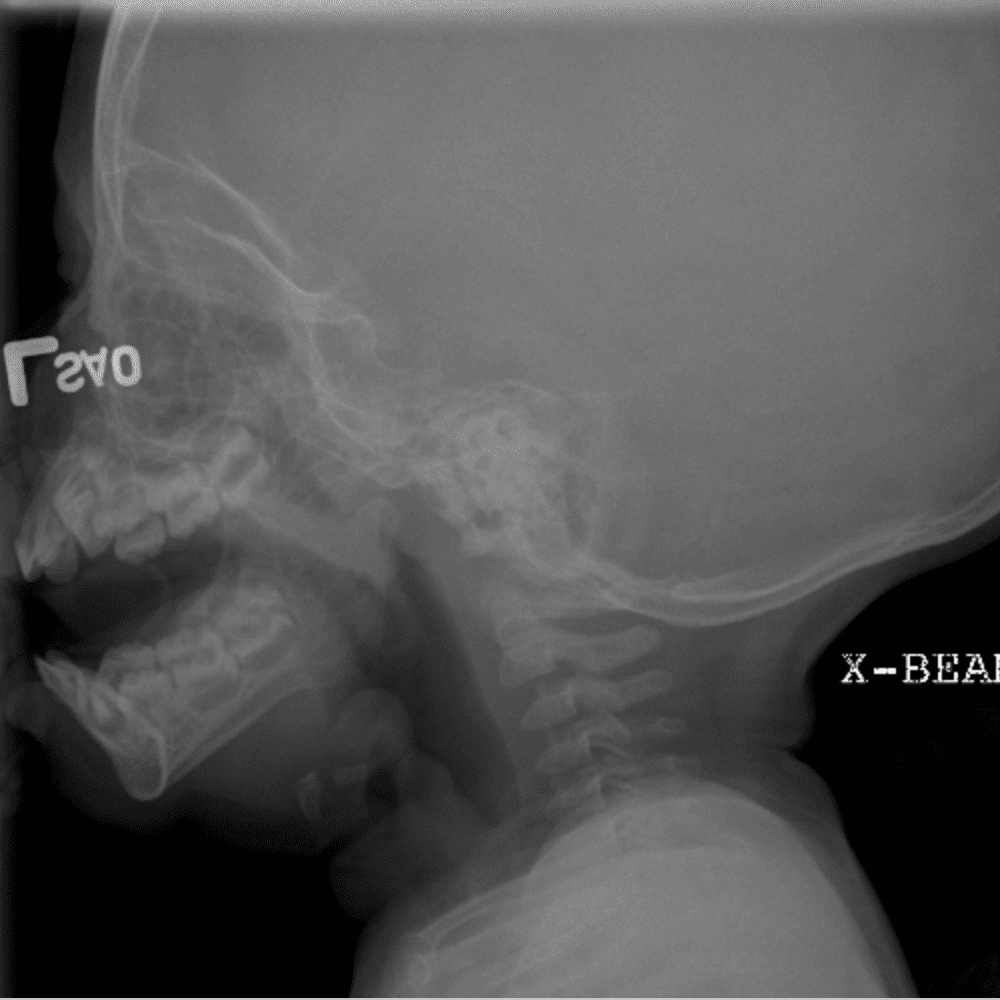

Peds Chest

Practice

Simulates call by including subtle or difficult cases and some normals.

50 cases